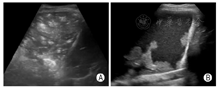

病例3:男,50岁,因"尿少2年,心累、气促1月、发热、咳嗽2天"入院,体温最高38.5 ℃。2020年1月15日院外胸部CT示:双肺散在模糊小结节,双肺下叶感染,双侧胸腔少量积液;2020年1月2日院外复查CT示:双肺感染灶明显进展,呈散在结节斑片影,部分结节内可见空洞,空洞内可见内容物;2020年2月4日复查CT:双肺散在斑片、磨玻璃、点结、纤维条影,密度不均,边界模糊,双侧胸腔少量积液,心包腔少量积液。既往有"肾功能不全尿毒症期""高血压病3级""2型糖尿病"等。1月前因慢性肾功能衰竭在武汉某三甲医院ICU住院治疗17天,于2020年1月13日到成都某医院因重症肺炎、病毒性肺炎、慢性肾病住院治疗8天后,以"新型冠状病毒肺炎疑似患者"到定点医院隔离治疗,后核酸检测阳性确诊(本病例由成都市公共卫生医疗中心提供,图14)。